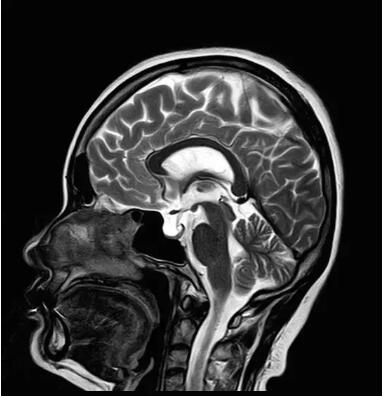

此技術(shù)主要用于神經(jīng)系統(tǒng)惡性腫瘤,以及其他腫瘤腦轉(zhuǎn)移瘤篩查。傳統(tǒng)情況下做腫瘤腦轉(zhuǎn)移篩查,很容易漏掉5mm以下小病灶,臨床發(fā)現(xiàn)后干預(yù)治療比較晚,要實(shí)現(xiàn)2mm高空間分辨率和超薄層全腦掃描在保證信噪比的情況下需要很長(zhǎng)時(shí)間大概十多分鐘,而且薄層增強(qiáng)序列顱內(nèi)血管呈高亮信號(hào),會(huì)干擾顱內(nèi)小病灶的觀察,血管和小病灶區(qū)分困難。佳能”螢火蟲”成像技術(shù)既可以實(shí)現(xiàn)高空間分辨率和超薄層(最薄可實(shí)現(xiàn)0.2mm)全腦掃描,掃描時(shí)間短,2-3分鐘即可實(shí)現(xiàn)全腦3D掃描,同時(shí)避免了血管高亮信號(hào)的干擾,對(duì)顱內(nèi)原發(fā)或繼發(fā)的微小腫瘤檢查有重大意義。“螢火蟲”成像技術(shù)具有磁敏感效應(yīng),對(duì)于亞急性血敏感敏感,可以區(qū)分出血和強(qiáng)化的腫瘤。